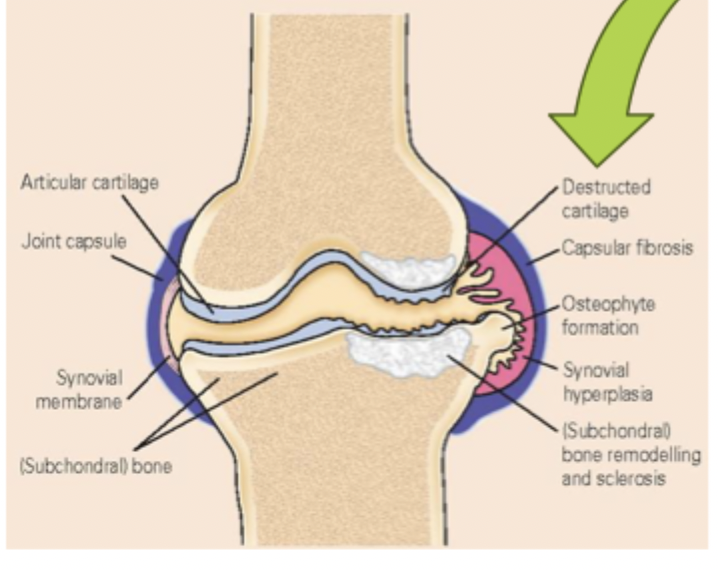

Osteoarthritis (OA)

The most common cause of chronic disability due to pain and altered joint function that mostly affects middle-age or elderly people (40+) due to the “wear and tear” of the joints

Subchondral bone, cartilage, ligaments, capsule, synovial membrane, and surrounding muscle

OA involves what parts of the joint

osteophytes (making joints swollen, painful, and stiff)

Breakdown of cartilage in joint causes bone-on-bone action and may lead to

pro-inflammatory mediators (macrophage 1 - joint destruction), Anti-inflammatory cytokines (macrophage 2 - repair damage)

OA is characterized by the presence of ______________ and __________________